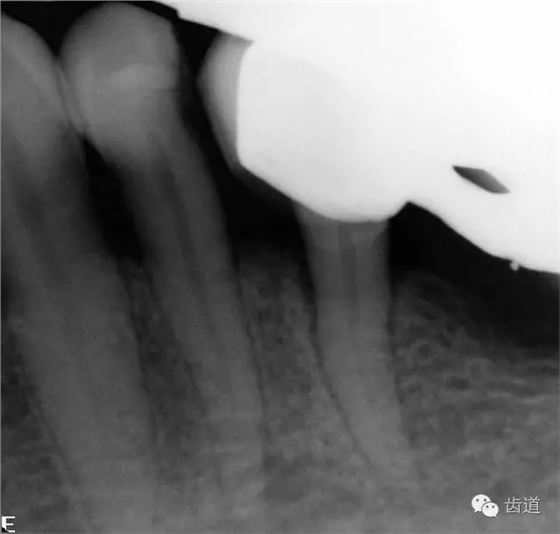

2、45,46術(shù)前片顯示根管上段充填物,根管影像不清晰,少許根尖暗影

1、45,46牙體缺損,慢性根尖周炎(不良根管治療術(shù)后)